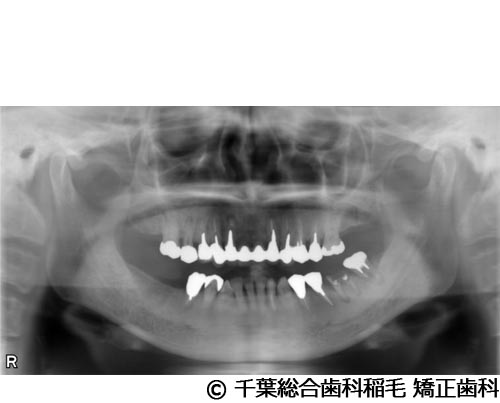

【症例3】上下5本インプラント埋入手術

- 治療前

- 治療後

- 治療名

- 上下5本インプラント埋入手術

- 費用

- 2,500,000円(税込)

- 期間

- 11ヵ月

治療内容

-

患者様の症状

欠損歯が多いため、お食事が取りにくく、インプラント治療のご相談でご来院されました。

治療法

状態の悪かった歯も含め、上下5本インプラントを埋入しました。

治療結果

奥歯でしっかり噛めるようになったと喜んでいただけました。

現在も定期健診で拝見させていただいています。

※治療結果は患者様によって個人差があります。